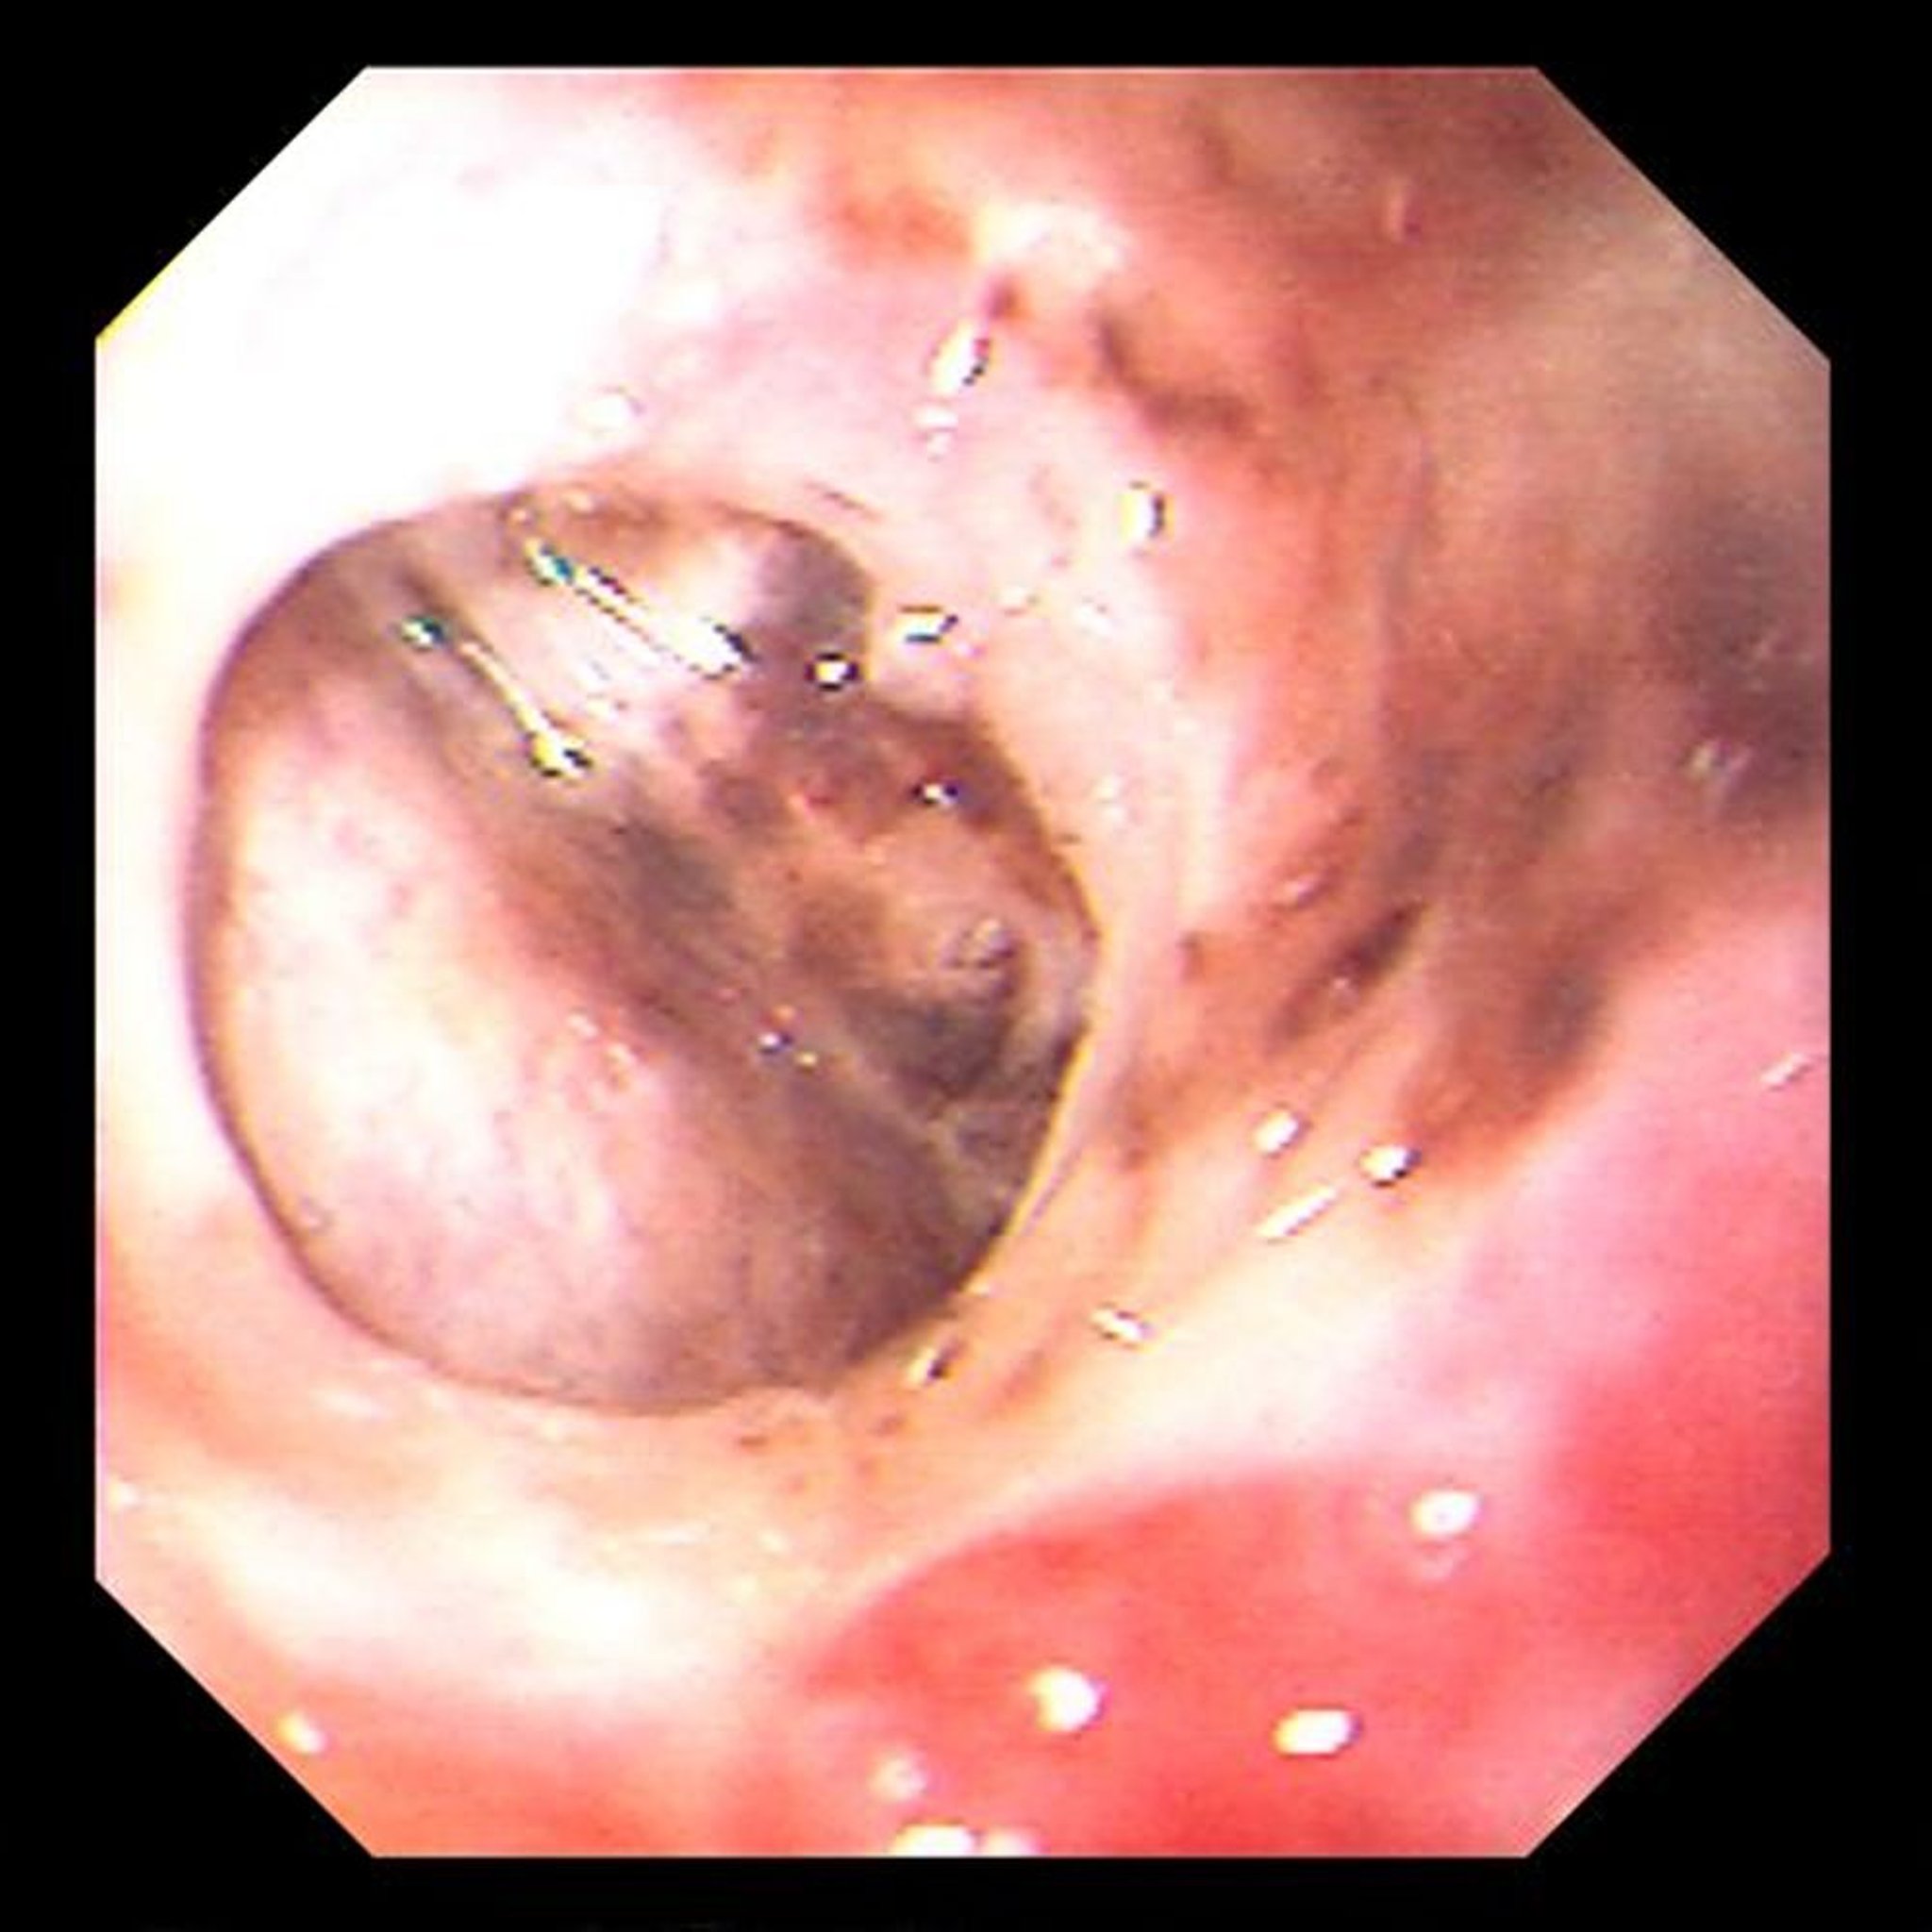

This image shows chronic, confined, gastric ulcer perforation through which the liver is visible.

Image provided by David M. Martin, MD.